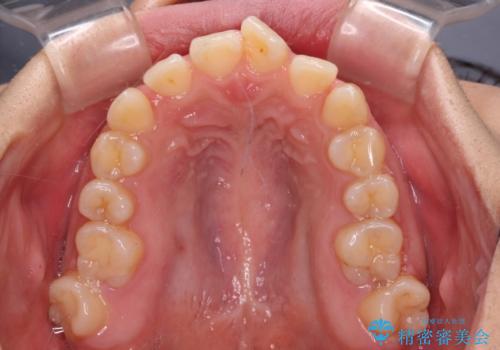

- 上下の前歯が非接触であることと、それに伴う口元の閉じにくさを気にして来院された患者様です。

奥歯の咬み合わせを見ると、上顎が下顎に対して相対的に前方にありました。

口元の閉じにくさを改善するためには、上顎臼歯を後方に移動させた咬み合わせにする必要があります。

インビザライン単体で改善することも可能ですが、達成する可能性が高くないため、カリエールディスタライザーという補助装置を併用して、より確実性を上げることとしました。

奥歯の咬み合わせを改善しながら、並行してインビザラインで歯列を整えることとしました。